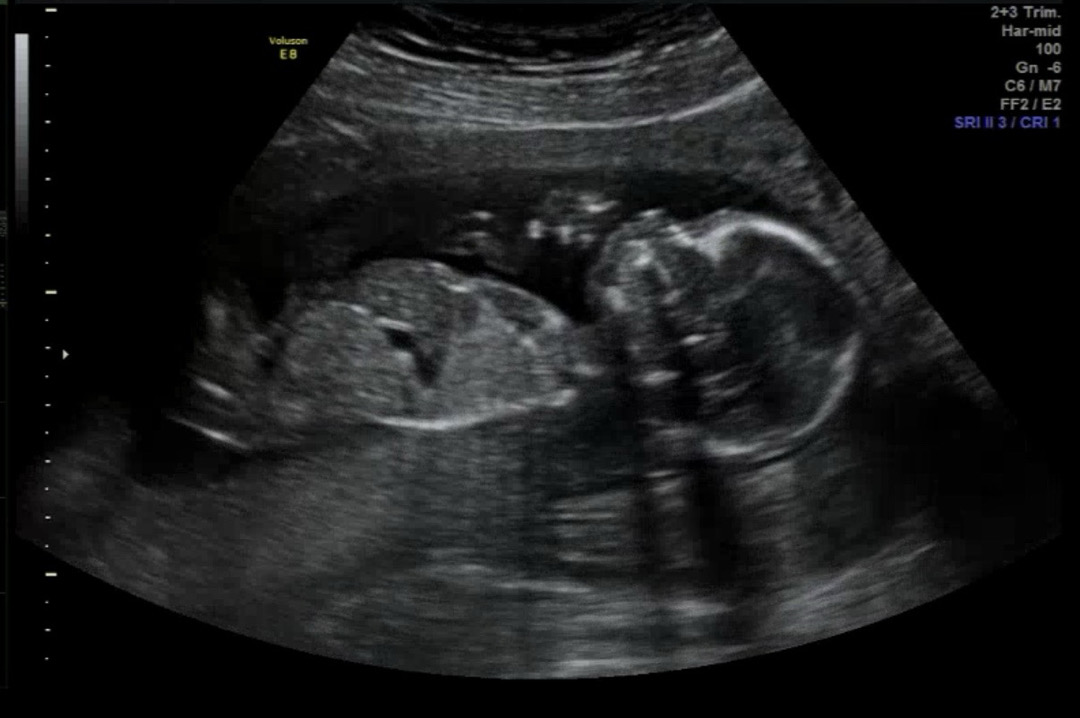

16주 아들 누워있는 모습 심쿵..🩵

무려 5주만에 진료 보고 왔어요..🥹 기다리느라 진짜 목 빠지는줄 알았는데 다음 진료도 또 5주후 정밀춈파네요..🫠 얼른 태동이 느껴졌으면 좋겠어요🥹🥹🥹